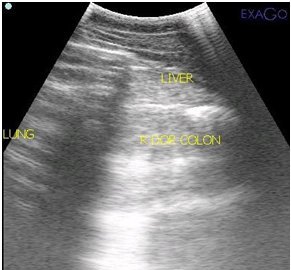

Digital Ultrasound

A high quality ultrasound is a very valuable imaging tool for evaluating and diagnosing a wide range of conditions primarily but not limited to soft tissue. Musculoskeletal structures such as tendons, ligaments, joints, muscles and bone surfaces may be evaluated for signs of injury or infection. Once an injury is found, ultrasound allows for monitoring healing progress. It can be used for ultrasound guided injections of structures such as the sacroiliac and cervical joints. Ultrasound can aid in diagnosing the cause of colic and other abdominal conditions as well as conditions of the thorax such as pleuropneumonia and lung abscesses. Another very common use of ultrasonography is to monitor reproductive cycles and pregnancy in the broodmare.